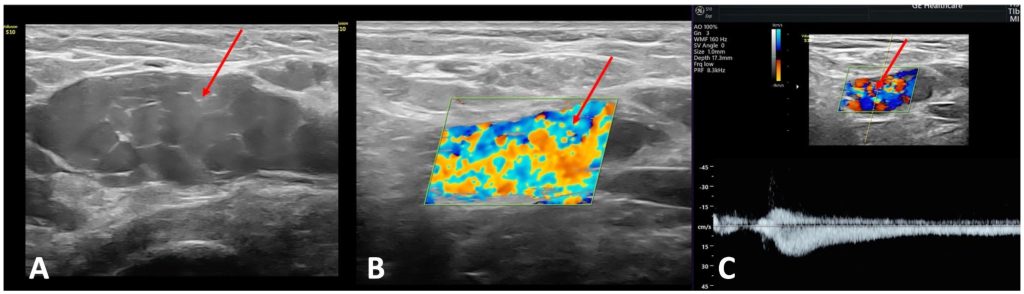

Оно играет важнейшую роль в исключении альтернативных причин хронической тазовой боли, особенно гинекологических заболеваний, таких как эндометриоз, аденомиоз, кисты яичников и миомы. Наличие расширенных тазовых венозных сплетений и вены шириной более 5 мм, пересекающей тело матки и соединяющей расширенные периматочные венозные сплетения с обеих сторон матки (рис.3), считается высокочувствительным и специфичным признаком заболеваний вен малого таза.[3].

тазовый варикоз

Рисунок 3. (А) Варикозно расширенные вены периматочного венозного сплетения (желтая стрелка), расположенные рядом с маткой и соединенные с веной, проходящей через тело матки (красная стрелка). (B) Рефлюкс (продолжительность: 2 с) в околоматочном венозном сплетении (желтая стрелка) после дистального ручного компрессионного воздействия в ипсилатеральной подвздошной ямке.